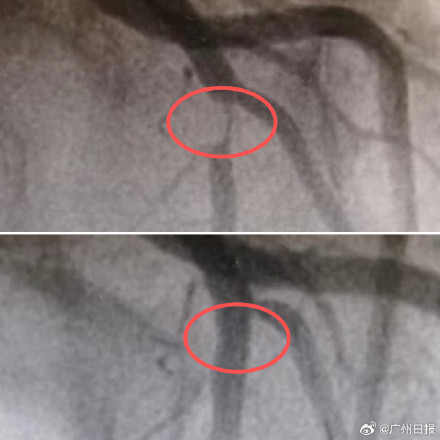

近日,浙江杭州,27岁女子小欣觉得活动后会有点胸闷,两天后情况也未缓解,于是前往就医,确诊为急性前壁非ST段抬高型心肌梗死。随后的造影结果,让在场的医生都替小欣捏了把汗:心脏上最重要的一根血管前降支已经堵了95%,只剩下一条细细的缝供血,随时都有完全堵死的风险。医生在小欣堵塞的血管处植入了一枚支架,撑开了狭窄的通道,恢复了心脏的供血,把她从“悬崖边”拉了回来。 医生介绍,小欣是典型的“现代青年”。在问诊中,她提到自己喜欢吃高热量的食物,每天少不了奶茶、重口味饭菜和外卖。工作时久坐,在家喜欢躺着刷剧,平时疏于运动……后果是小欣的体重增至近200斤,还查出2型糖尿病。医生表示,这些高危因素叠加在一起,导致其血管更早地出现问题,发生心梗也就不足为奇了。(浙医在线)